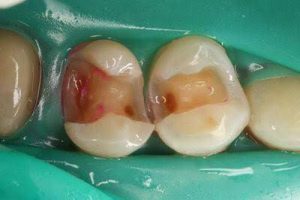

う蝕部分にカリソルブを塗布することで、う蝕組織のみに薬剤が作用し軟化します。

専用のインスツルメントでやわらかくなった組織を取り除き、詰め物をするだけで治療は終了です。